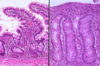

Normal Small Intestine

Normal Small Intestine